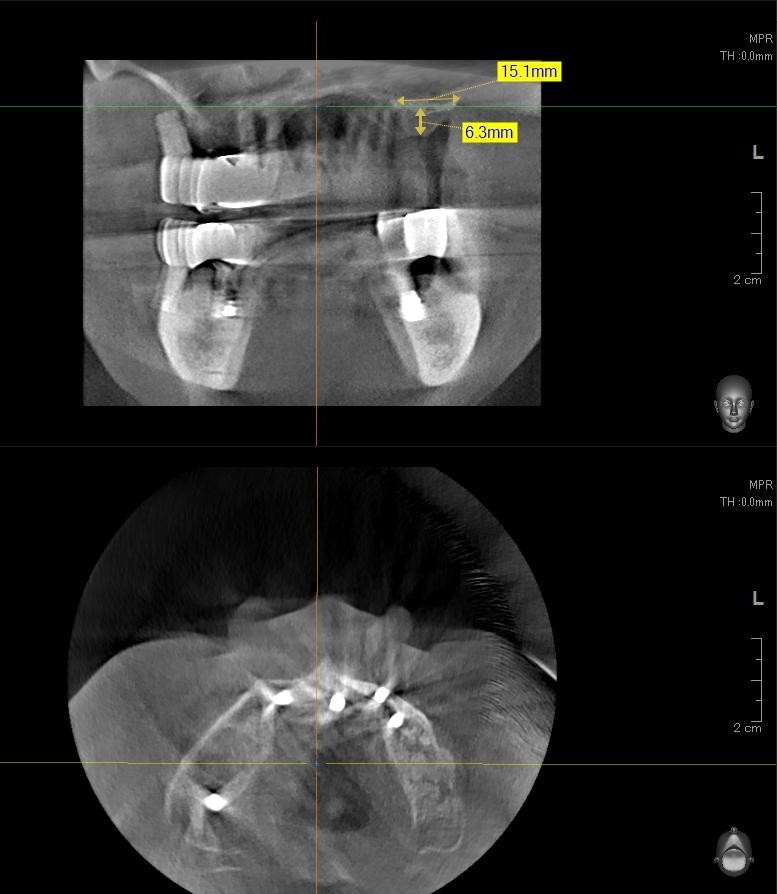

今回の患者様はインプラント植立を希望され、左上6番目・7番目の2本の植立が決まりました。

しっかりとインプラント埋め込まれた後は、動揺がないか、噛んだ時に当たらないかなどを確認して、最後にパノラマ写真を撮影して今回のオペは終了となりました。